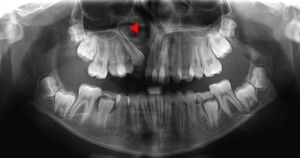

نتوء سنخي

Alveolar process | |

![]() Anterior (frontal) part of maxilla (white) and mandible (orange) cut away towards right (to depth of tooth roots, i.e. the alveolar region) | |

The alveolar process ( []ælˈviːələr,_ˌælviˈoʊlər,_ˈælviələr[])[1] is the portion of bone containing the tooth sockets on the jaw bones (in humans, the maxilla and the mandible). The alveolar process is covered by gums within the mouth, terminating roughly along the line of the mandibular canal. Partially comprising compact bone, it is penetrated by many small openings for blood vessels and connective fibres.